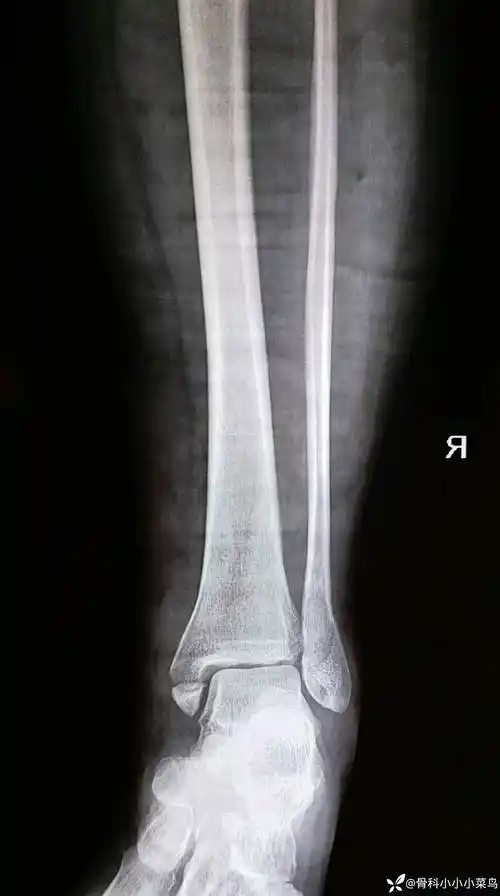

后踝撕脱骨块处理还是不处理